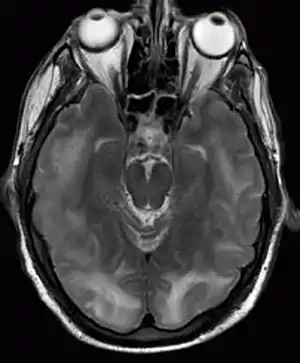

| Posterior reversible encephalopathy syndrome visible on magnetic resonance imaging as multiple cortico-subcortical areas of T2-weighted hyperintense (white) signal involving the occipital and parietal lobes bilaterally and pons. | |

The diagnosis is typically made with magnetic resonance imaging of the brain. The findings most characteristic for PRES are symmetrical hyperintensities on T2-weighed imaging in the parietal and occipital lobes; this pattern is present in more than half of all cases.[1][2] FLAIR sequences can be better at showing these abnormalities.[3] Some specific other rare patterns have been described: the superior frontal sulcus (SFS) watershed pattern, a watershed pattern involving the entire hemisphere (holohemispheric), and a central pattern with vasogenic oedema in the deep white matter, basal ganglia, thalami, brainstem and pons.[1][2] These distinct patterns do not generally correlate with the nature of the symptoms or their severity, although severe edema may suggest a poorer prognosis.[1] If the appearances are not typical, other causes for the symptoms and the imaging abnormalities need to considered before PRES can be diagnosed conclusively.[3] In many cases there is evidence of constriction of the blood vessels (if angiography is performed), suggesting a possible overlap with reversible cerebral vasoconstriction syndrome (RCVS). Diffusion MRI may be used to identify areas of cytotoxic edema caused by poor blood flow (ischemia) but it is not clear if this prognostically relevant.[1][3] Abnormal apparent diffusion coefficient is seen in about 20% of cases.[3]